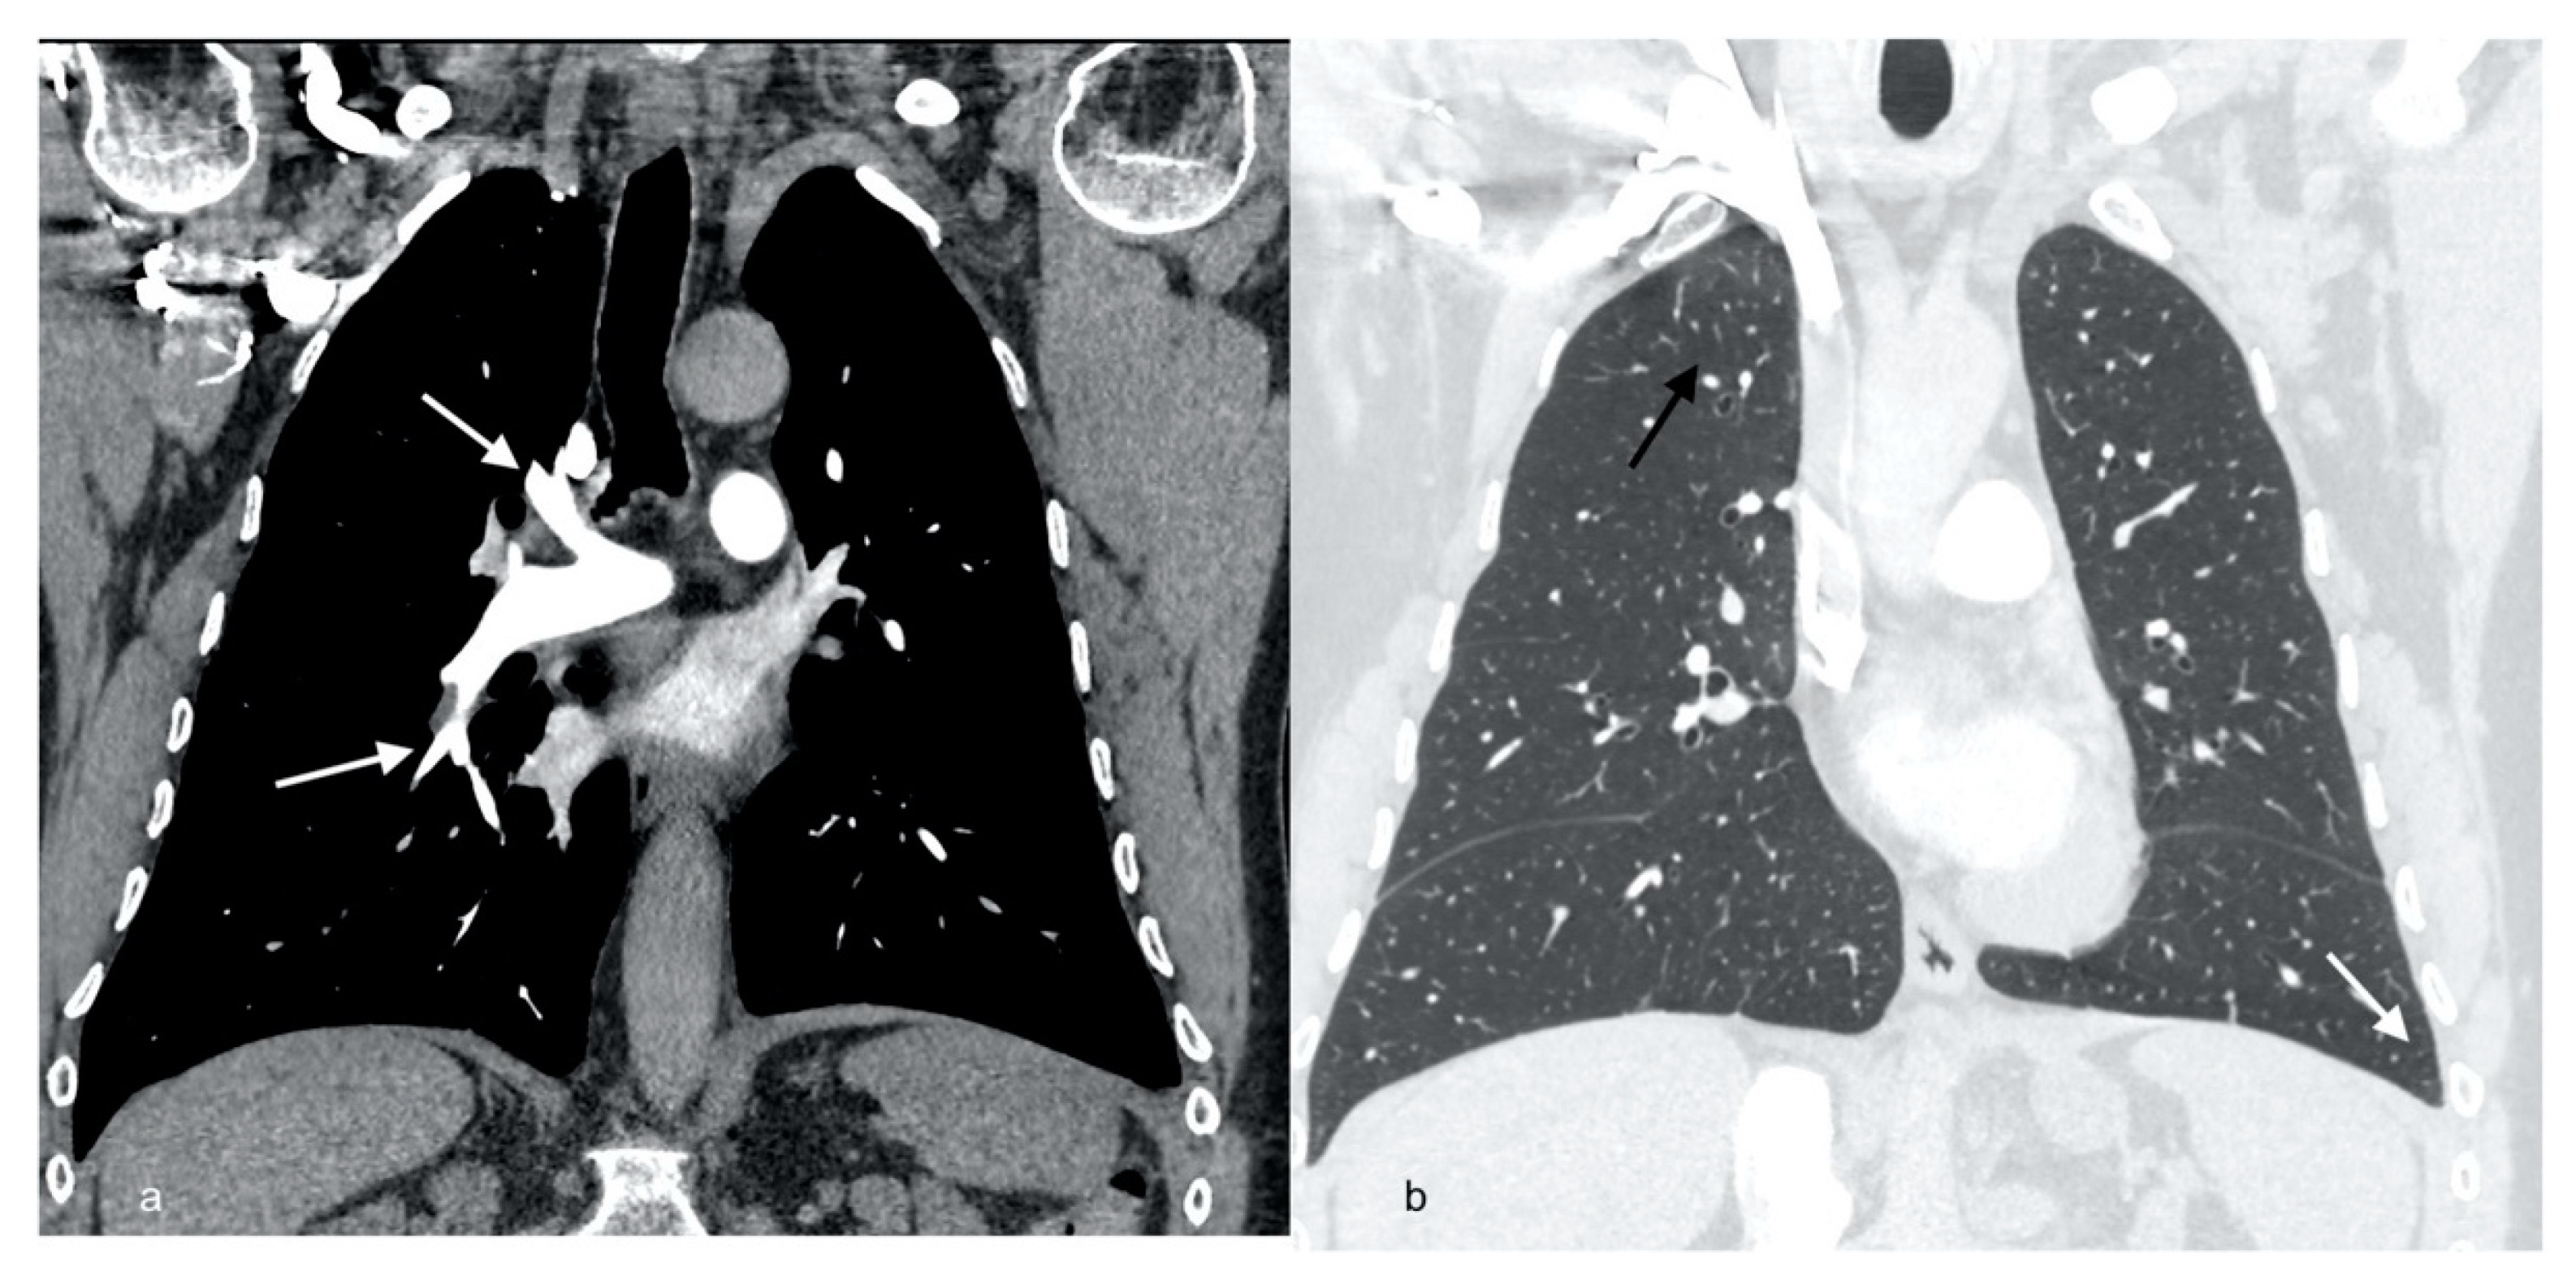

| Radiological picture | Pulmonary embolism, parenchymal infiltrates, bilateral pleural fluid | Regression of PA thrombi, pleural fluid and parenchymal consolidations | Complete resolution of PA thrombi, pleural fluid and lung consolidations | |